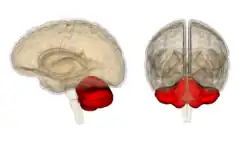

Cerebelo

El cerebelo es conocido por su participación en la ejecución de movimientos y por su capacidad para perfeccionar la agilidad motora necesaria en las habilidades procedimentales, como la pintura o la interpretación musical. Los daños en esta área pueden impedir el reaprendizaje de las habilidades motoras, y recientes estudios lo han relacionado con el proceso de automatización inconsciente de las habilidades durante la fase de aprendizaje.[31] Algunas corrientes de pensamiento sugieren que la corteza cerebelar contiene las huellas de memoria conocidas como engramas, o al menos supone el espacio biológico en el que se almacenan los recuerdos. Se piensa que la huella inicial de memoria se forma en esta estructura, y después viaja a otros núcleos cerebrales a través de las fibras paralelas conocidas como células de Purkinje, para su posterior consolidación.[32]